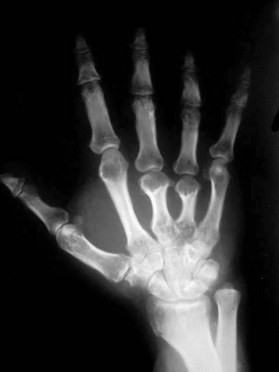

SIGNO DEL METACARPO

En sujetos normales, el trazado de una línea tangencial a los extremos distales de las cabezas del cuarto y quinto metacarpianos, se extiende distalmente a la cabeza del tercero. Sin embargo, cuando la línea corta la cabeza del tercer metacarpiano (signo del metacarpiano positivo) es por que existe un marcado acortamiento de los metacarpianos cuarto y quinto. Este hallazgo puede verse en el pseudohipoparatiroidismo, pseudo-pseudohipoparatiroidismo, disgenesia gonadal, hipertiroidismo neonatal, síndrome del nevus de células basales, displasia epifisaria múltiple, síndrome de Beckwith-Wiedemann, anemia de células falciformes , artritis reumatoide juvenil y traumatismos.

En la imagen puede verse el marcado acortamiento de los metacarpianos del tercer y cuarto dedo en un paciente con pseudohipoparatiroidismo.

Imagen de una radiografía normal de la mano para comparar la altura de los metacarpianos.